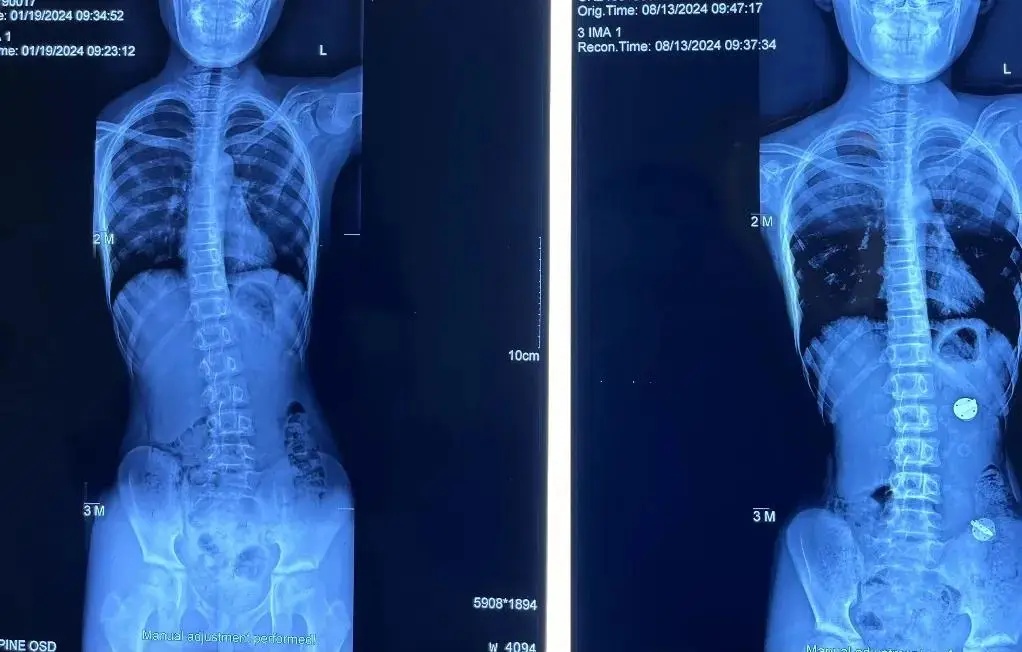

康复医学科“青少年脊柱侧弯矫正冬令营”开营啦!